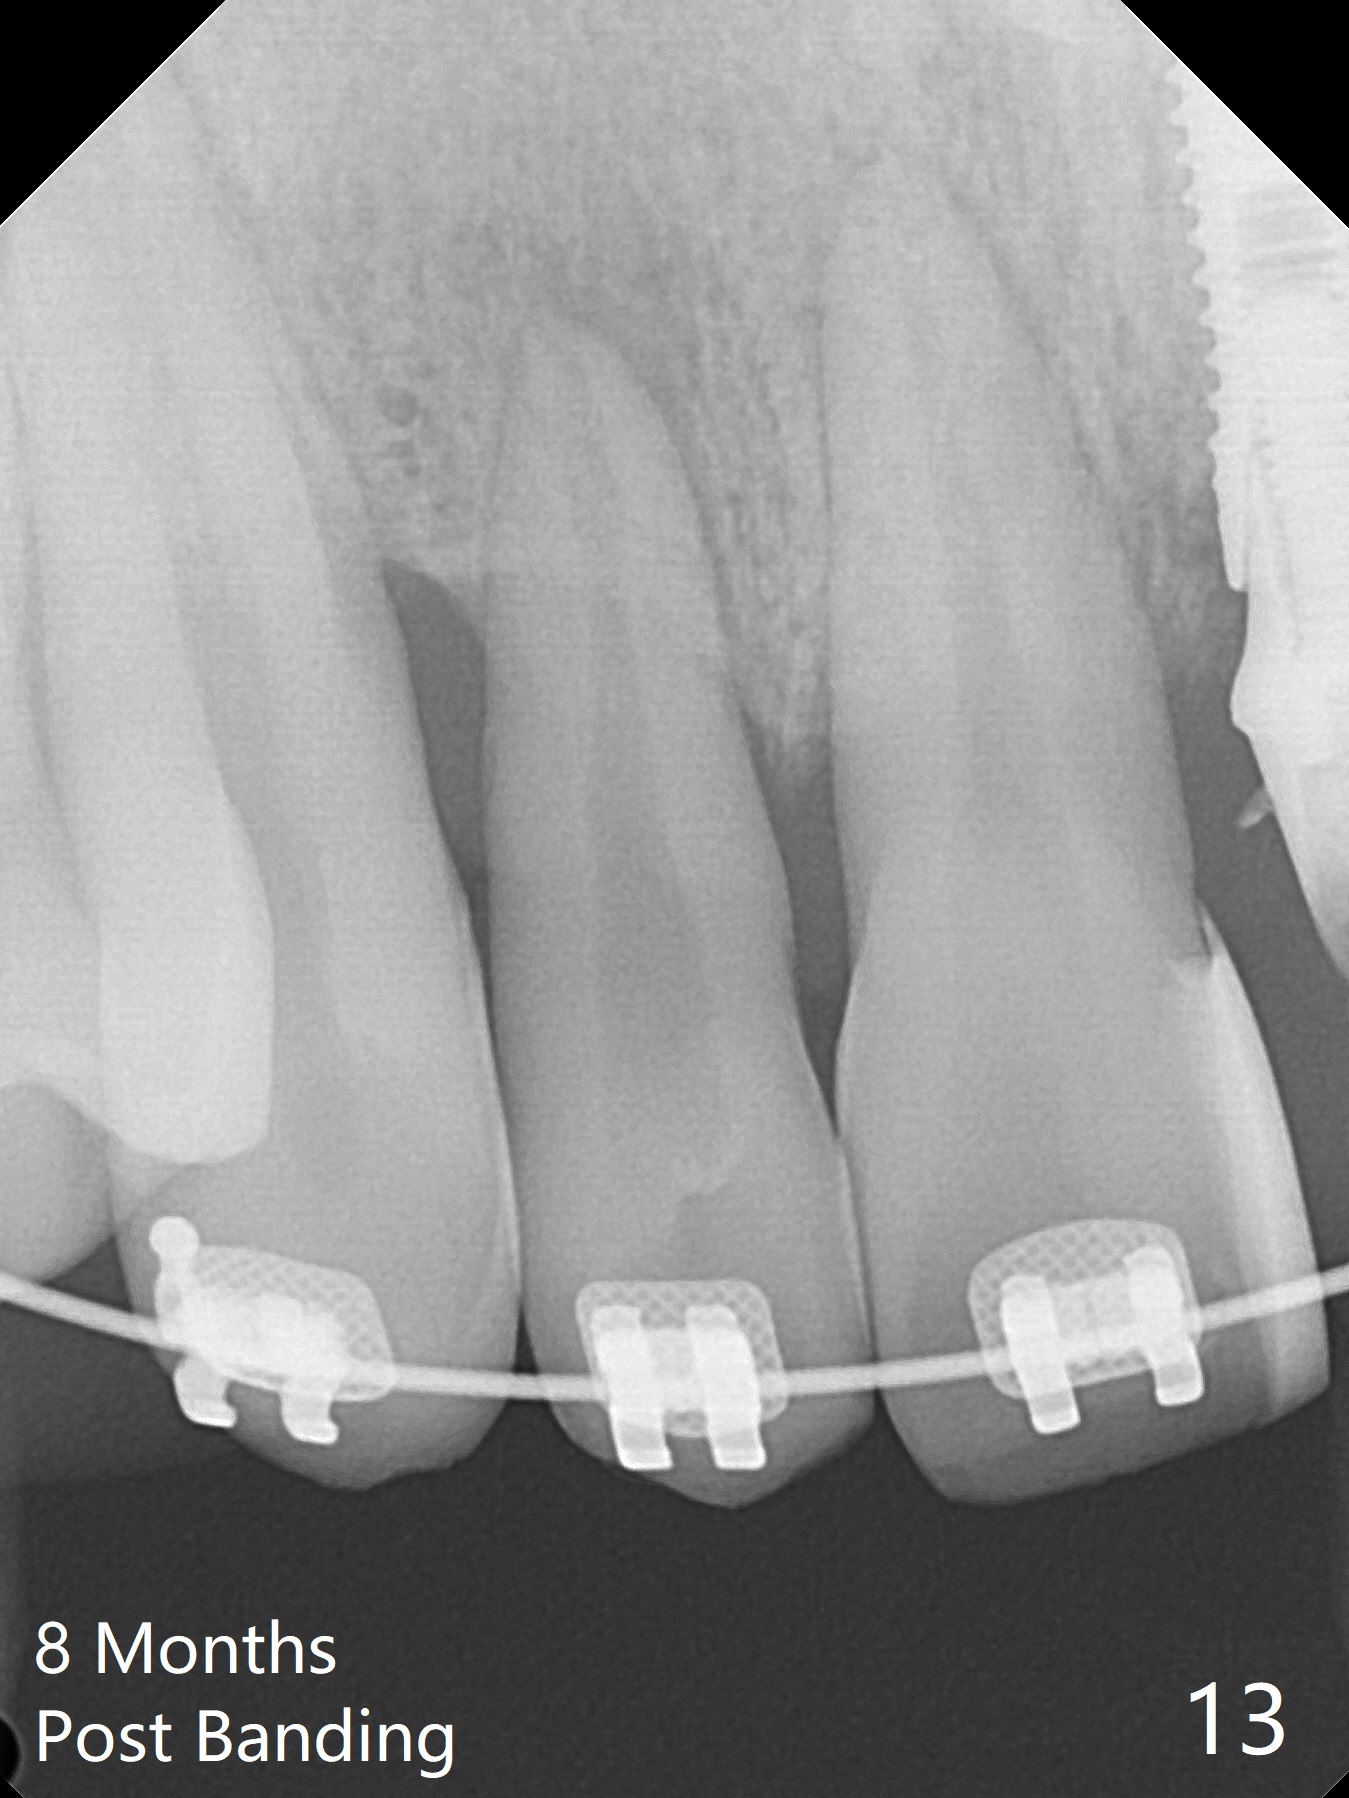

Limited Ortho with Proximal

Reduction

Nearly 7 months postop, the immediate provisional at UL1 is removed; with the mesial reduction of UL2 from 7 to 6 mm (Fig.1), an angled abutment is to be changed (4.5x15 degree, 2 mm cuff). A new provisional (Fig.2,3) co-incides with the facial midline. Brackets will be placed between UR4 to UL3 except UL2 (symptomatic once with chronic periodontitis) with initial proximal reduction between UR1-4 in preparation to correct cross bite of UR2. Twelve days later, the patient returns for UR5-UL3 bracketing after UR1-4 initial proximal reduction with 14 niti wire (Fig.4-6). UR1 moves mesial 20 days post open coil spring (Fig.7 arrow), while UL1 debracketes after permanent re-cementation of the temporary crown last visit (*, no re-bracketing, since it appears not essential). Before placement of 20 ss wire, diastemata are created by proximal reduction (Fig.8 *). In fact UR1 moves mesial, while UR3 does not move distal with the open coil. With placement of UR6 (implant) molar band, UR3 is distalized effectively. With sling shot, UR2 is almost labialized in one appointment (Fig.9). After consolidation of the diastemata between UR1-6 with power chains following UR2 cross bite correction (Fig.10), the restoration space for UL1 seems to be too large (Fig.11). Next visit, check the midlines, take 1-2 PAs for #7-9 and determine whether a straight abutment should be changed back and whether composite should be placed UR1 mesial to reduce the space. One week later, composite is added to the mesial surface of the tooth #8 to increase its width, while the provisional at #9 is relined to improve the interdental papilla (Fig.12). Minimal bone loss at UR2 is observed 8 months post banding (Fig.13), while the socket at UL1 seems to have healed except the most coronal 1 year 3 months postop (Fig.14 *). The margin of the abutment should be uneven, more coronal proximal than buccopalatal (Fig.15). The final crown has an open margin, partially due to less ideal trajectory (Fig.16 (black line: ideal trajectory, nearly 1 year 4 months postop)). Guided surgery could solve the problem. Sticky bone may restore the buccal plate defect. Die shows that the implant is palatally placed (Fig.17). CT will be taken to determine whether the implant perforates the palatal plate.